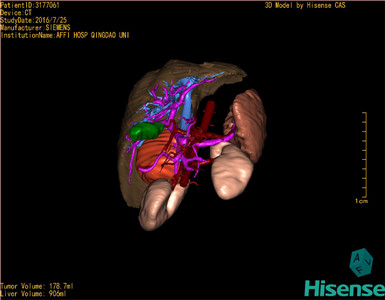

将0.625mm双源薄层CT资料的静脉期和动脉期Dicom格式文件导入海信CAS系统。

通过调节窗宽窗位调整CT序号,对肿瘤,肝实质,胆囊,下腔静脉,肿瘤,肝动脉、门静脉及肝静脉等进行三维重建;系统自动计算肿瘤体积和肝脏体积。

模拟手术操作,自动计算切除肿瘤体积。肝脏体积为906ml,肿瘤体积为178.7ml,肿瘤体积为肝脏体积的19.7%,通过比对6-9月正常肝脏体积为257.75±51.05ml,通过术前模拟手术,精准判断切除后剩余肝脏体积能耐受,避免肝衰竭发生。

术前三维重建:

重建图片